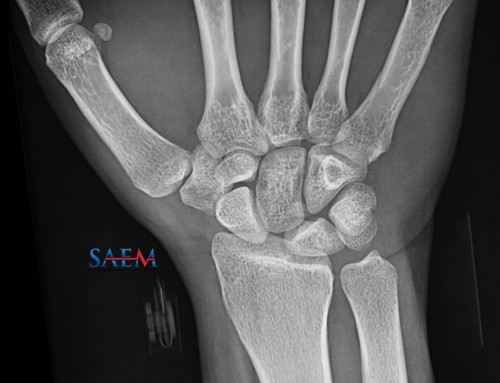

Given her pain with range of motion at her hip, you order a hip radiograph, but while waiting for it, decide to perform a hip point of care ultrasound (POCUS) examination.

The patient’s hip plain film radiographs are unremarkable. You decide to incorporate hip POCUS to your evaluation. You place a linear, high-frequency transducer and visualize the patient’s bilateral hips. You observe the following: